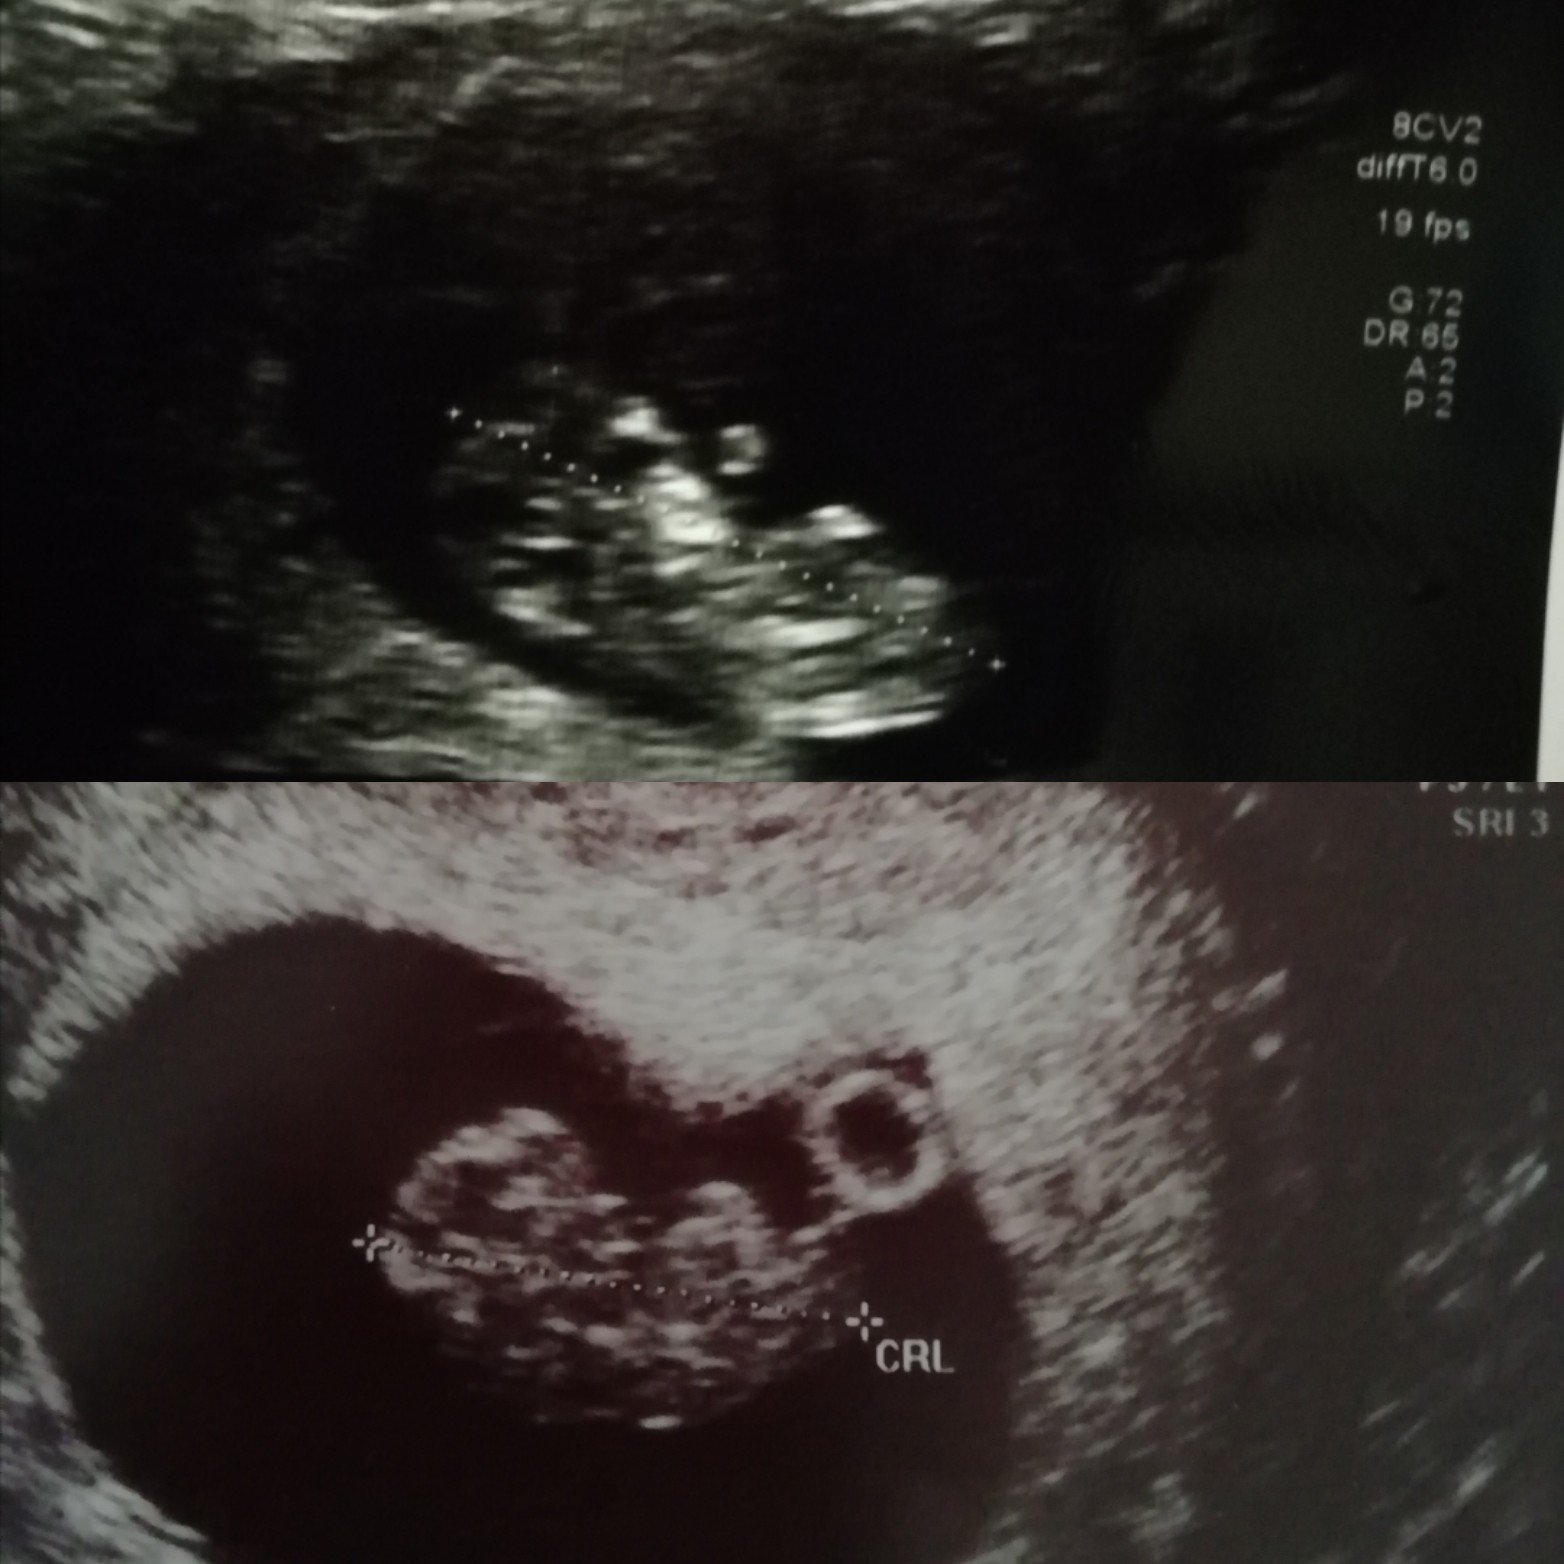

Widziałam rączki, stopki, słyszałam serduszko ❤ Na pierwszym zdjęciu dostałam kopniaka, a na drugim pokazuje, że jest mu w brzuszku ok, czyli była pełna komunikacja

Lekarka mówiła że jest prawie całkowicie pewna, że to chłopak, ale jeszcze się pod tym nie podpisze

Wiem, że marzysz o chłopcu i tego@paulina.blachut tak mi zasialas ziarno tymi zgadywankimi. Że normalnie wyszukalam foto mojego synka z 9+4 na górze i porównał z obecną dzidziom 9+0 x) późno żeby co kolwiek analizować, ale no są innepróbowałaś zerknąć na foto swojej córki i obecne?Zobacz załącznik 1001474